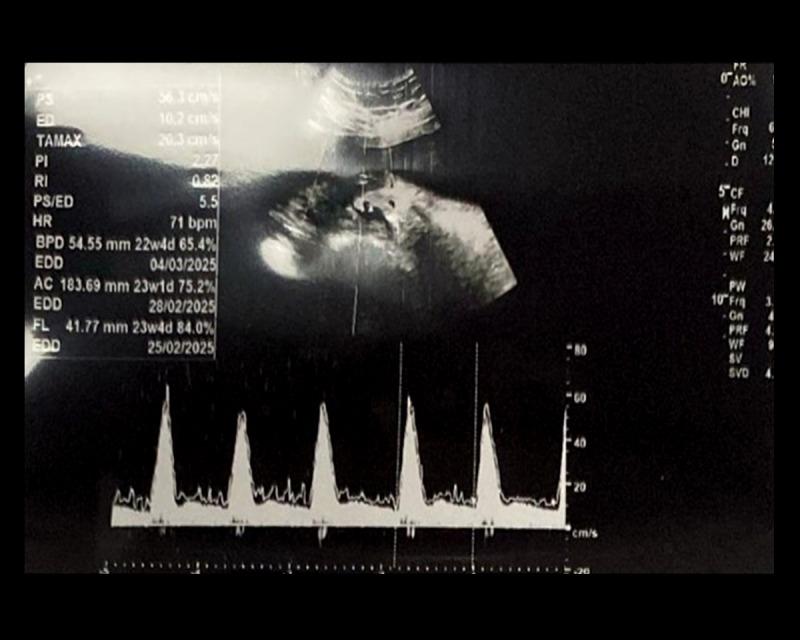

BACKGROUND Magnesium and calcium are essential minerals for both maternal and fetal health during pregnancy, with their balance potentially influencing uterine artery function. This study explores the connection between serum magnesium and calcium levels and the presence of a diastolic notch in uterine artery Doppler ultrasonography during the second trimester, a marker that could have significant clinical implications for pregnancy outcomes. MATERIAL AND METHODS In this prospective study, conducted from July 31, 2022, to February 28, 2023, we assessed 60 primigravida women between 18 and 24 weeks of gestation. We measured serum magnesium and calcium levels and analyzed their relationship with diastolic notch presence in uterine artery Doppler ultrasonography, a potential indicator of placental vascular resistance. RESULTS Participants had an average age of 25.7±3.67 years and a BMI of 25±4.02. The mean serum magnesium level was 1.77±0.26 mg/dL, while the mean serum calcium level was 9.1±0.63 mg/dL. Notably, serum magnesium levels were significantly lower in the diastolic notch group compared to the non-notch group (p=0.048), and serum calcium levels were significantly higher in the diastolic notch group (p=0.002). CONCLUSIONS This study suggests a significant association between the presence of a diastolic notch in uterine artery Doppler ultrasonography and altered serum levels of magnesium and calcium. These findings may provide a predictive marker for placental dysfunctions such as preeclampsia and intrauterine growth restriction. Further large-scale studies are needed to confirm these associations and explore their clinical utility.

在这项前瞻性研究中,于2022年7月31日至2023年2月28日进行,我们评估了60名妊娠18至24周的初产妇。我们测量了血清镁和钙水平,并分析了它们与子宫动脉多普勒超声检查中舒张期切迹的关系,舒张期切迹是胎盘血管阻力的一个潜在指标。

参与者的平均年龄为25.7±3.67岁,BMI为25±4.02。血清镁平均水平为1.77±0.26mg/dL,而血清钙平均水平为9.1±0.63mg/dL。值得注意的是,舒张期切迹组的血清镁水平显著低于无切迹组(p=0.048),舒张期切迹组的血清钙水平显著高于无切迹组(p=0.002)。